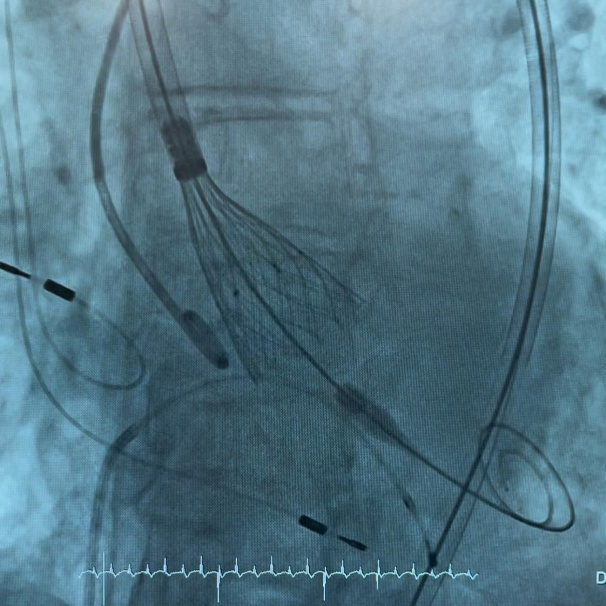

在IMPERIA?输送系统获批后联合ALLEGRA?于西班牙、德国完成全球首植后不久,意大利也传来喜讯,于那不勒斯Pineta Grande医院成功实现IMPERIA?输送系统与ALLEGRA?的联合植入。该植入针对一位高龄女性患者,由Arturo Giordano博士、Nicola Corcione博士、Michele Albanese博士和Alberto Morello博士团队完成,蓝帆柏盛国际团队现场支持。

该患者是一名83岁的女性,植入后获得卓越的临床结果:术前平均跨瓣压差:40 mmHg;术后平均跨瓣压差:8 mmHg;术后无瓣周漏发生。

放置中